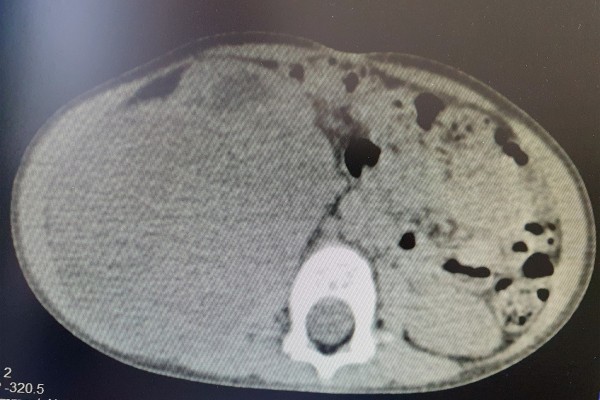

Shërbimi Spitalor Klinik dhe Universitar i Kosovës ka njoftuar se në Klinikën e Kirurgjisë së Fëmijëve të Qendrës Klinike Universitare të Kosovës, mjekët kirurgë, të asistuar nga ekipi i anestezionit, kanë operuar me sukses një fëmijë të moshës 2 vjeçare, duke ia larguar tumorin, i cili ia kishte përfshirë gjysmën e barkut.

“Operacioni u realizua, pas trajtimit dhe ekzaminimeve të vazhdueshme nga mjekët pediatër-onkologë. Pacienti është në gjendje të mirë shëndetësore dhe pritet të lirohet shumë shpejt për në shtëpi”, thuhet në njoftimin e SHSKUK-së.